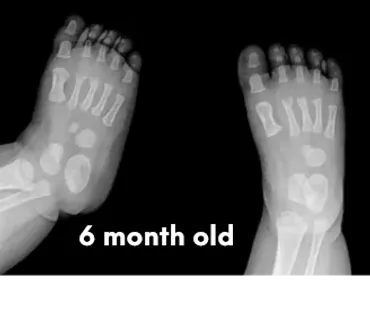

Babies’ feet are very soft and mostly made of cartilage in the first years of life. Their bones are still forming, and they have a thick layer of fat that makes their feet look chubby. This is why it’s important not to restrict their feet with tight or rigid shoes, as it could affect the natural shape and growth.

The pictures below will let you understand how babies' feet are developed. Here you can see how bones develop:

6 Months

18 YearsDear parents, children’s feet are developing structures, and the absence of an arch is a typical stage of development. Detailed X-RAY pictures above let us understand that babies' foot bones are not connected till the teen years. Only at the age of 14 may we consider that the bones in the feet have reached their connections. At the age of 18, we have fully completed foot structure, where muscles and bones create the whole support system.